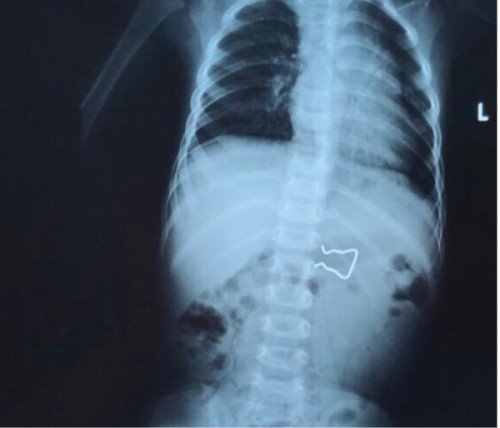

Bé 18 tháng tuổi nuốt móc sắt vào ruột, cha mẹ hốt hoảng đưa đi cấp cứu

Kết quả chụp X-quang cho thấy dị trong ruột bệnh nhi là vật dùng để cố định trong kẹp quần áo, có 2 cạnh sắc...